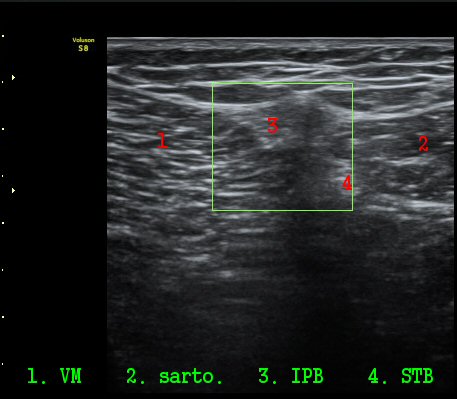

¹«¸­ ³»Ãø Á¾´Ü¸é°Ë»ç»ó ½ÉÇÑ °ñ±Ø°ú ¹Ý¿ù»ó¿¬°ñ Ç¥ÃþÀ¸·Î µ¹ÃâÀÌ °üÂûµÊ(»çÁø 1)

´ëÅð ³»Ãø, ¹«¸­ °üÀý¸é¿¡¼­ ¾à 10 cm ±ÙÀ§ºÎȾ´Ü¸é°Ë»ç¿¡¼­ ³»Ãø±¤±Ù°ú ºÀRHD±Ù(sartorius)

»çÀÌ¿¡¼­ º¹Àç½Å°æÀÌ °í¿¡ÄÚ Å¸¿øÇü ¾ç»óÀ¸·Î °í³ªÂûµÈ´Ù(»çÁø 2).